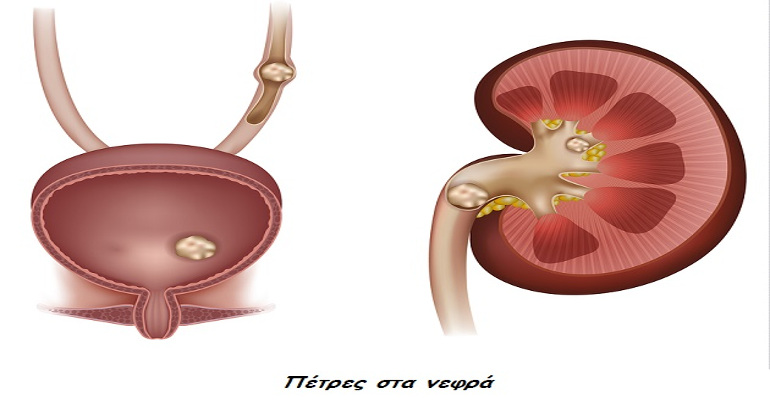

Ελλάδα Κέντρο Αιμοκάθαρσης: Ο απίστευτος παράγοντας που συμβάλλει σε έμφραγμα, εγκεφαλικό και νεφροπάθεια

Ερευνητές από το Πανεπιστήμιο της Αριζόνα διαπίστωσαν ότι ένας «ύπουλος» παράγοντας μπορεί να υπονομεύσει σημαντικά την υγεία μας και να μας βάλει μελλοντικά σε κίνδυνο, καθώς αυξάνει τις πιθανότητες να πάθουμε έμφραγμα ή εγκεφαλικό και να εμφανίσουμε πρόβλημα στα νεφρά ή τα μάτια.